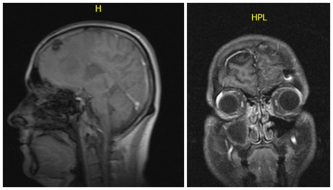

Pojechałem samochodem do banku, ja, zdrowy 27-letni facet. Do domu już nie wróciłem. Atak padaczki, który nadszedł, powalił mnie na ziemię, straciłem przytomność. Obudziłem się w szpitalu, do którego przywiozło mnie pogotowie. Znów przed oczami obraz, który nie zdążył zniknąć z pamięci. Szpitalne jasne światło, zdenerwowani lekarze, nerwowe szepty i decyzje, zapadające jedna po drugiej. Wiedziałem, co oznacza rezonans, bo to wynik tego badania rozpoczął walkę mojej siostry ze śmiercią. Teraz nie mogło być tak samo, to przecież niedorzeczne, zbyt groteskowe, zbyt okrutne.

Glejak IV stopnia - tak brzmiał mój wyrok, z którym żyję od 2014 roku. Tak brzmiał wyrok dla mojej mamy, która traci drugie dziecko. Ta choroba nie ma dla nas tajemnic i nie ma litości. Śmiertelny guz atakujący mózg, który pojawia się nagle i znikąd. Nie masz czasu się przygotować, bo na śmierć nie można się nastawić. Znaliśmy całą procedurę, znaliśmy szanse i wszystkie możliwości. Nie da się opisać tego, jak czuje się człowiek, który dostaje wyrok śmierci, nie da się też opowiedzieć, czy jest różnica, kiedy przyjmuje się taką wiadomość w wieku 27 lat, a kiedy jest się już starym. Najbardziej żal było mi mamy. To ona cierpiała chyba najmocniej i to jej zawalił się świat, który tak misternie próbowała sobie odbudować po śmierci Agi. Teraz stanęła nad szpitalnym łóżkiem, w którym leżałem ja – jej do niedawna zdrowy, a teraz śmiertelnie chory syn.

Coraz częstszy, coraz bardziej nienaturalny. 8 grudnia, w tym magicznym i świątecznym miesiącu, pojechałem do szpitala, zrobiono rezonans i usłyszałem - naciek 7 cm po przeciwnej stronie mózgu niż ta zoperowana. Pierwszy raz w życiu poczułem pustkę. Pierwszy raz w życiu wydawało mi się, że nie będzie już nic dalej, że całe moje życie kończy się w tym dniu. Potem wszystko przyspieszyło, lekarze nie mogli się pogodzić z przegraną, mam przecież dopiero 30 lat. Trafiłem do szpitala w Rzeszowie. Po tej operacji na twarzach chirurgów nie było tego entuzjazmu, co poprzednio. Nie klepali mnie po ramieniu, nie uśmiechali się. Usunęliśmy tyle, ile się dało. Reszta musi zostać. To równoznaczne ze słowami: Dostał Pan czas, zanim nowotwór nie odrośnie. Może to będzie miesiąc może pół roku. To wciąż tak strasznie mało czasu, a ja przecież chcę żyć!